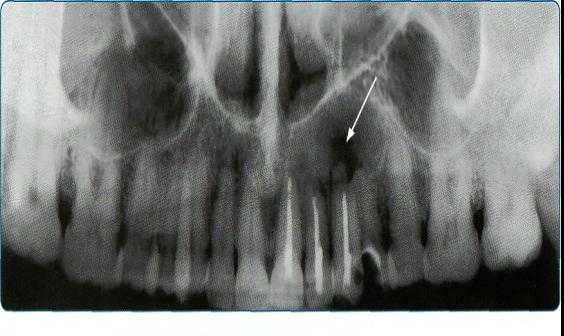

4. Панорамная томография

Более трех десятилетий назад в арсенал рентгенодиагностики заболеваний зубочелюстной системы, ЛОР-органов и других отделов черепа вошла панорамная рентгенография. При этом методе исследования аппликатор рентгеновской трубки вводят в рот пациента, а кассета располагается вокруг верхней или нижней челюстной дуги. В обоих случаях пациент придерживает кассету с наружной стороны ладонями, плотно прижимая ее к мягким тканям лица.

Проводится также и боковая панорамная томография, на боковом панорамном снимке одновременно отображаются зубы верхнего и нижнего ряда каждой половины челюсти.

Прямые панорамные рентгенограммы имеют преимущество перед внутриротовыми снимками по богатству деталями изображения костной ткани и твердых тканей зубов. При минимальной лучевой нагрузке они позволяют получить широкий обзор альвеолярного отростка и зубного ряда, облегчают работу рентгенолаборанта и резко сокращают время исследования. На этих снимках хорошо видны полости зуба, корневые каналы, периодонтальные щели, межальвеолярные гребни и костная структура не только альвеолярных отростков, но и тел челюстей. На панорамных рентгенограммах выявляются альвеолярная бухта и нижняя стенка верхнечелюстной пазухи, нижнечелюстной канал и основание нижнечелюстной кости.

На основании панорамных снимков диагностируют кариес и его осложнения, кисты разных типов, новообразования, повреждения челюстных костей и зубов, воспалительные и системные поражения. У детей хорошо определяется состояние и положение зачатков зубов.